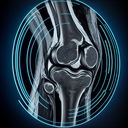

МРТ колінного суглобу

Магнітно-резонансна томографія (МРТ) колінного суглоба — це неінвазивний метод діагностики, який використовують для візуалізації внутрішньої структури коліна. Він допомагає виявити пошкодження зв'язок, менісків, хрящів та інших м'яких тканин, а також запальні процеси або новоутворення. Основні переваги МРТ колінного суглоба: - Висока точність і чіткість зображень...